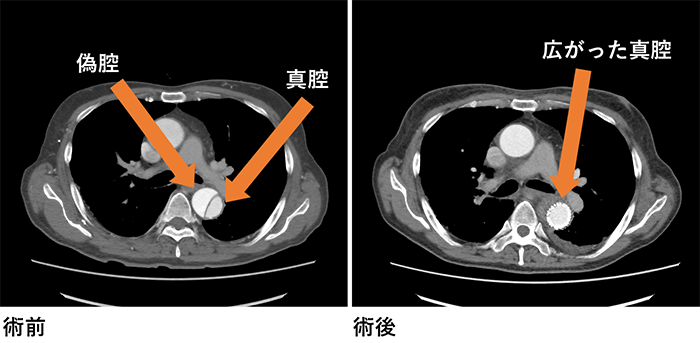

・開胸人工血管置換術、胸部ステントグラフト内挿術を患者様に応じて使い分けて治療を行っています。

・大動脈解離や弓部大動脈瘤ではフローズンエレファントトランクを積極的に活用して手術時間の短縮に努めています。

・ステントグラフトでZONE2からの1-Debranch TEVARが難しい症例はPhysician-Modified Stent GraftでZONE0から治療しています。

・B型解離で今後瘤拡大のリスクが高い患者様にPreemptive TEVARを行っています。